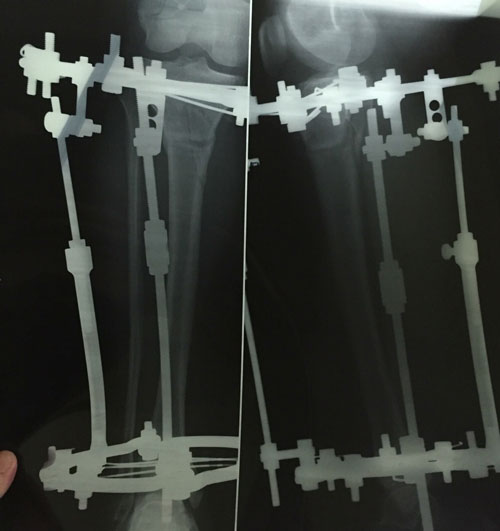

рентген в 90 дней.

Здравствуйте, Б.! Сращение идёт хорошо, но Вам ходить ещё месяц. в 120 дней ждём рентген.